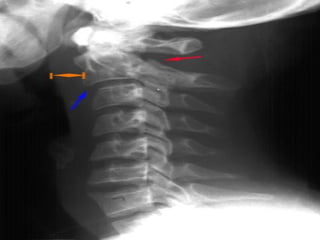

Key Things toIdentify  Predental space – should be 3mm or less

 Disc spacesshould be the equal and symmetric

 Prevertebral softtissue swelling  May be due to hematoma from a fracture  Soft tissue swelling may make fracture diagnosis difficulty

JEFFERSON FRACTURE  Compressionfracture of the bony ring of C1, characterized by lateral masses splitting and transverse ligament tear  Mechanism: Diving into shallow water, RTA  Best seen on Odontoid view  Signs: Displacement of the lateral masses of vertebrae C1 beyond the margins of the body of vertebra C2

 Radiographic features: thekey radiographic view is the AP open mouth, which shows displacement of the lateral masses of vertebrae C1 beyond the margins of the body of vertebra C2. A lateral displacement of >2 mm or unilateral displacement may be indicative of a C1 fracture. CT is required to define the extent of fracture and to detect fragments in the spinal canal. Stability: unstable

 the lateraldisplacement of C1 indicates a Jefferson fracture.

odontoid view, whichillustrates the lateral displacement of C1